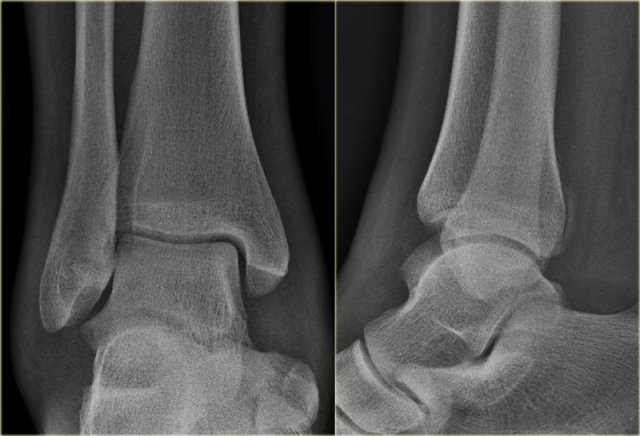

Study the images and then scroll to the next images.

The fracture through the epiphysis can be easily missed (blue arrow).

The fracture through the growth plate is only seen on CT.

Continue with the CT images.

The CT-images nicely display the fracture through the growth plate and the epiphysis.

This is also a Salter-Harris type III fracture.

Notice that there is also a Tillaux fracture.

We will discuss these fractures in a moment.